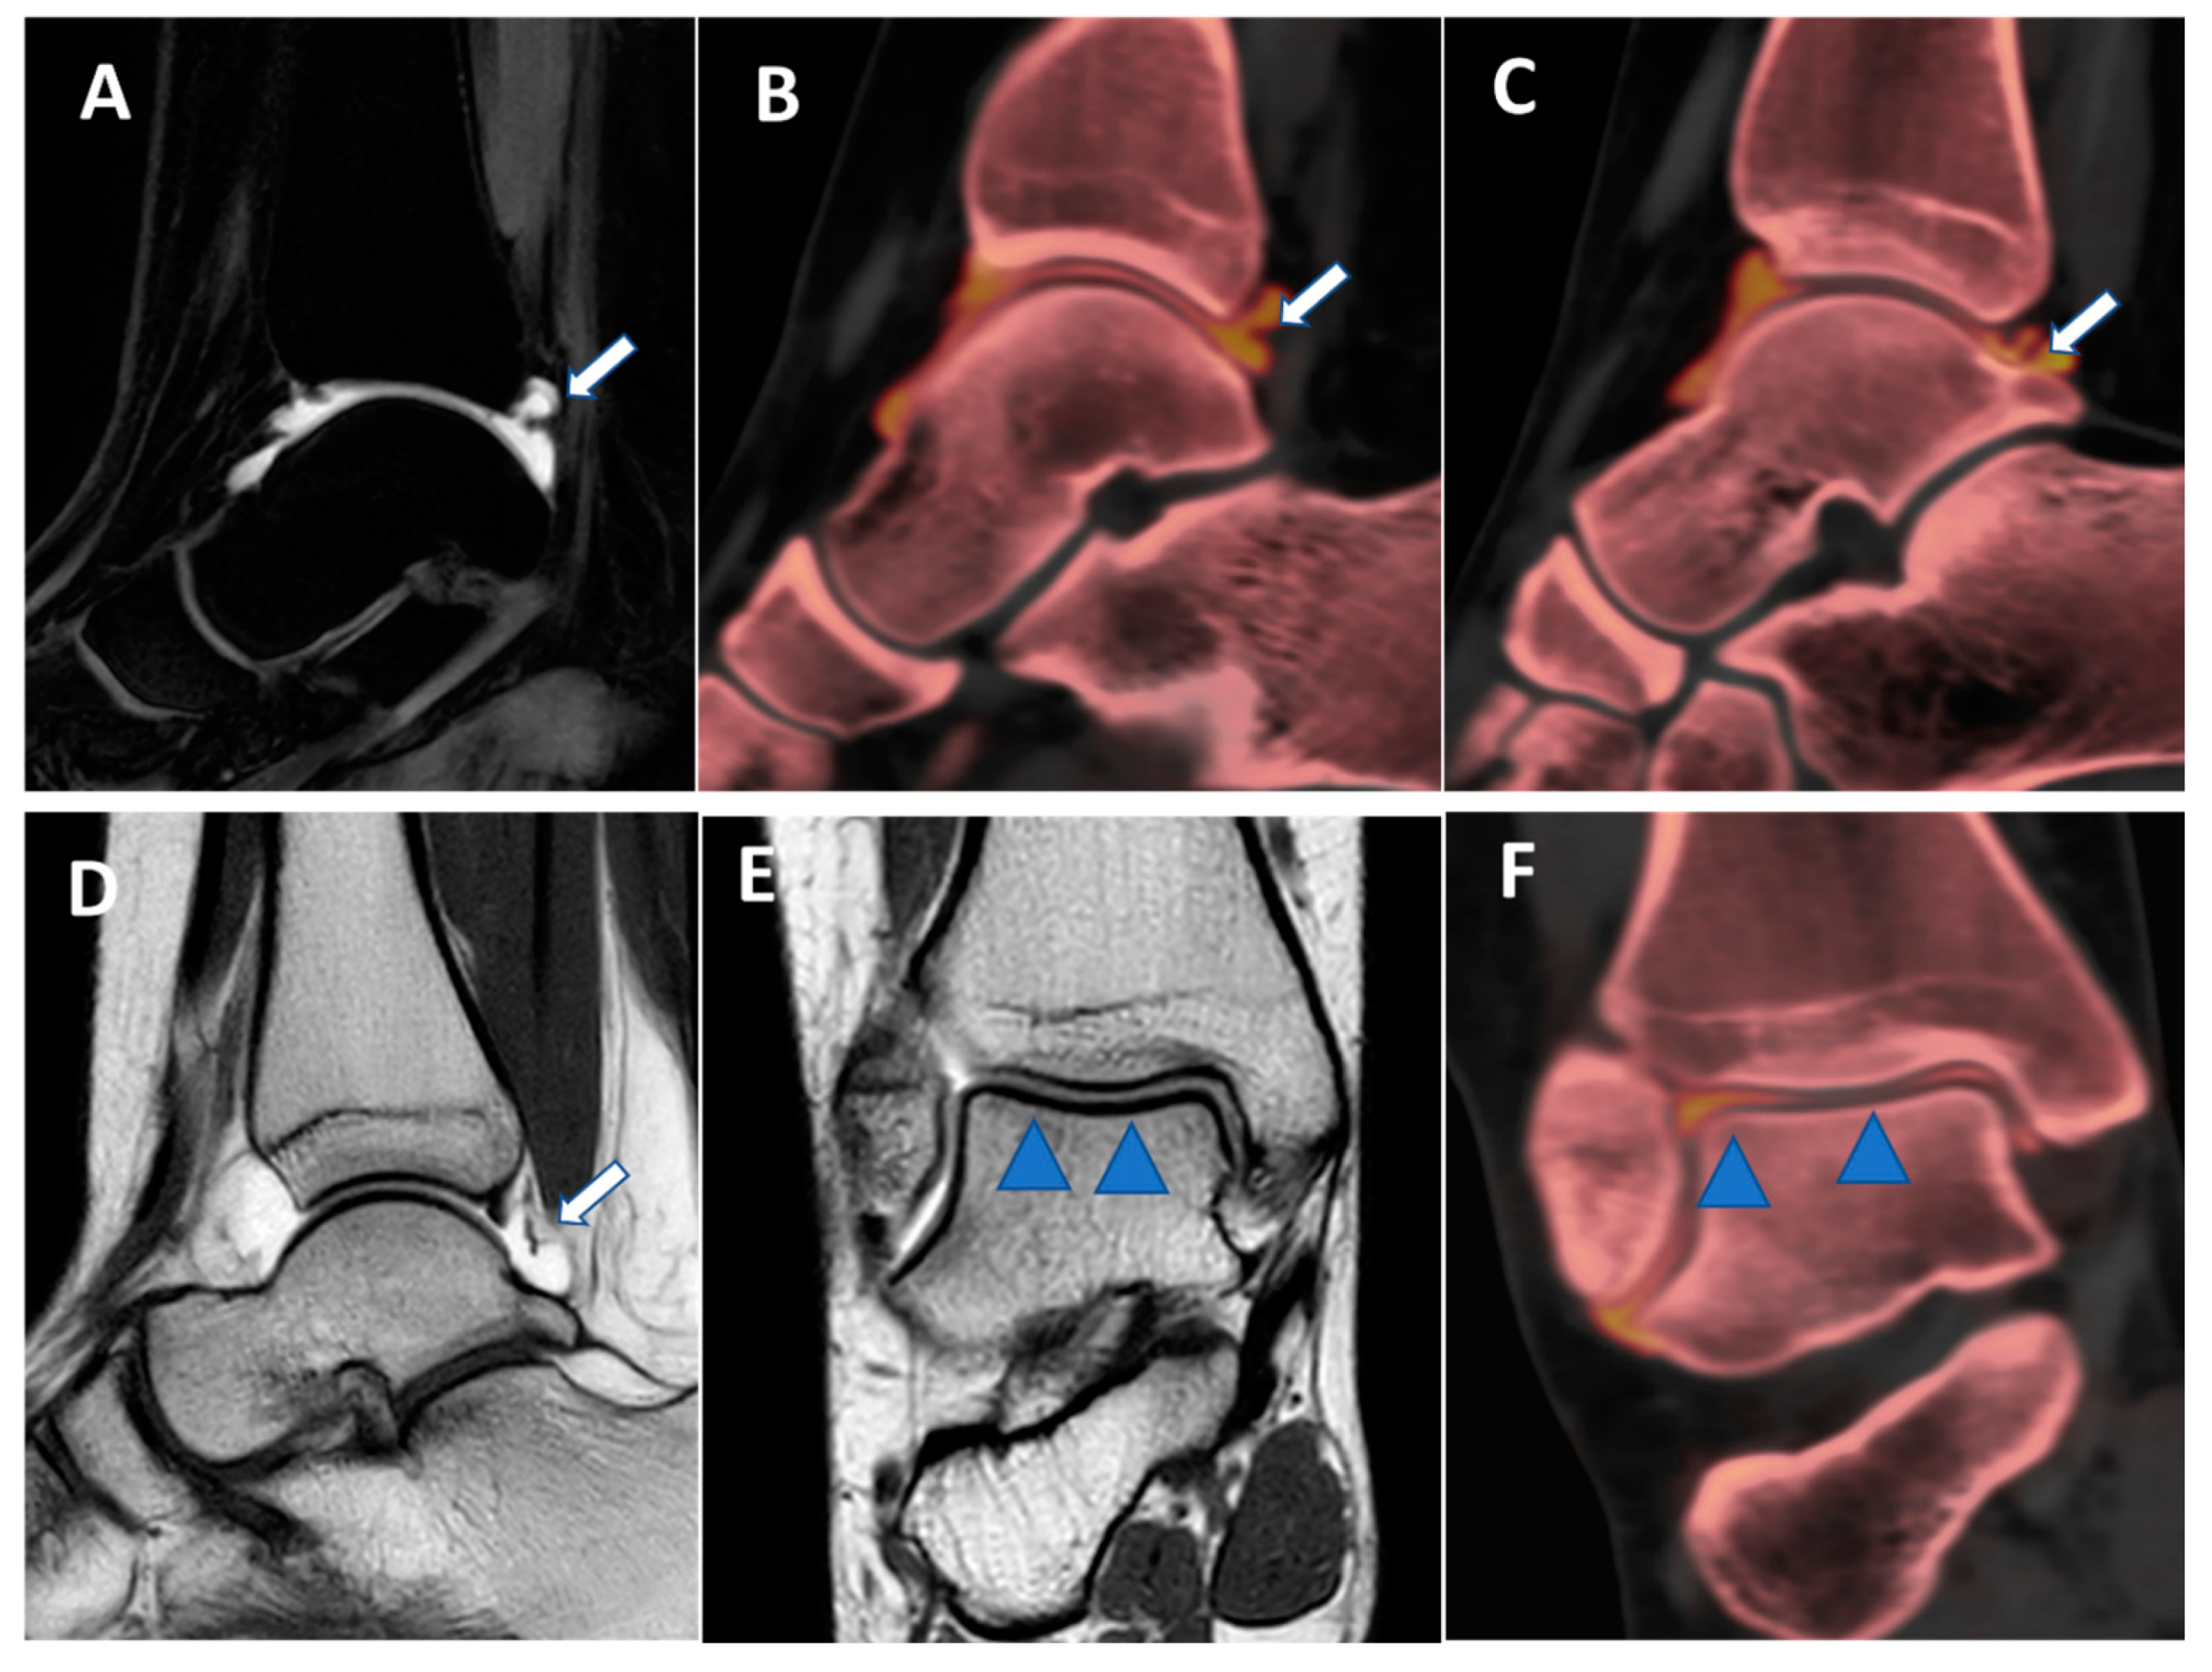

Figure 8. Posterior capsular plica at ankle arthrograms. On 3 mm sagittal STIR and T1 weighted images (A,D), a thin posterior plica (arrow) is depicted. The same plica is nicely depicted on the corresponding sagittal 0.3 mm DECT iodine map images (arrows on (B,C)). On 3 mm Coronal T1 weighted images (E), a partial volume effect may hinder subtle cartilage defects (blue arrowheads). On the corresponding 0.3 mm coronal DECTA (F), articular cartilages are optimally imaged without any artifacts.